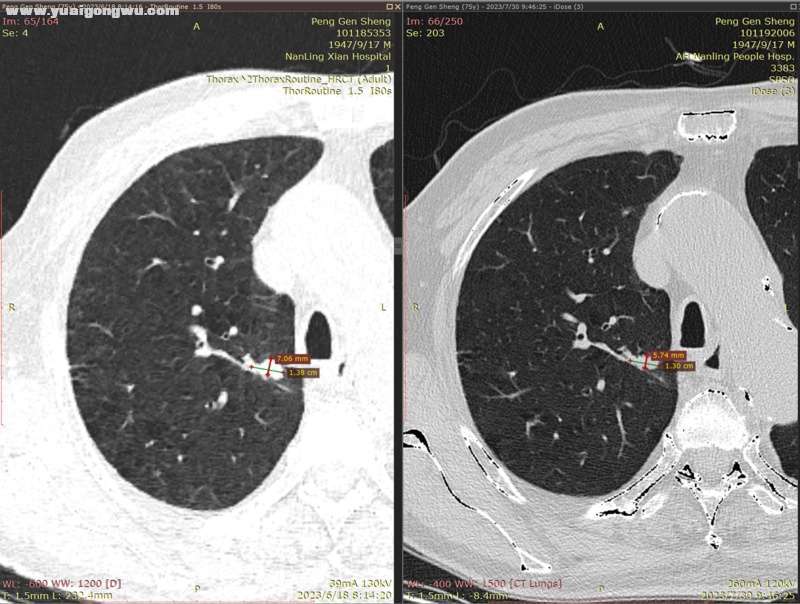

6月3日~7月29日,单用安罗替尼12mg(3周期),6月18日CT显示左肺主病灶稍缩(主病灶62mmx57mm);因近期有一点点吸不上气的感觉(吸氧后有缓解,其他身体体征正常,体感良好),7月30日CT显示左肺主病灶稍增大(主病灶68mmx62mm)。- L* L' w9 C: J7 b

影像科医生将7月30日的胸部CT,和6月18日的胸部CT电子影像对比分析如下:

2、右肺多发小结节,前面两枚之前重点关注的结节(有时变大有时变小),这次复查略微变小(图2~5;+ }% G% E$ F0 e  U; {- |' V' B

4、纵膈小淋巴结、肺部炎症情况基本没有变化。% y' R# g! n. ^# F) M8 n

* R5 w. e) k/ [9 Y( L' s' h* x* n7 d        以下为近两次CT影像的对比分析。7 Z8 B" @7 n7 B# ?+ K" ?( E( {) v